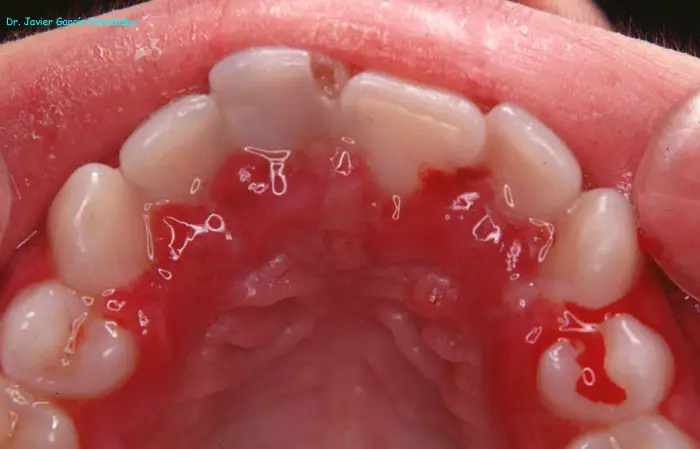

Atlas of Surgical Techniques in Periodontics. Chapter I. Diagnostic of Peridontal Diseases. Classification. Atlas de Técnicas Quirúrgicas en Periodoncia. Cap. I. Classification. Atlas de Técnicas Quirúrgicas en Periodoncia

image94